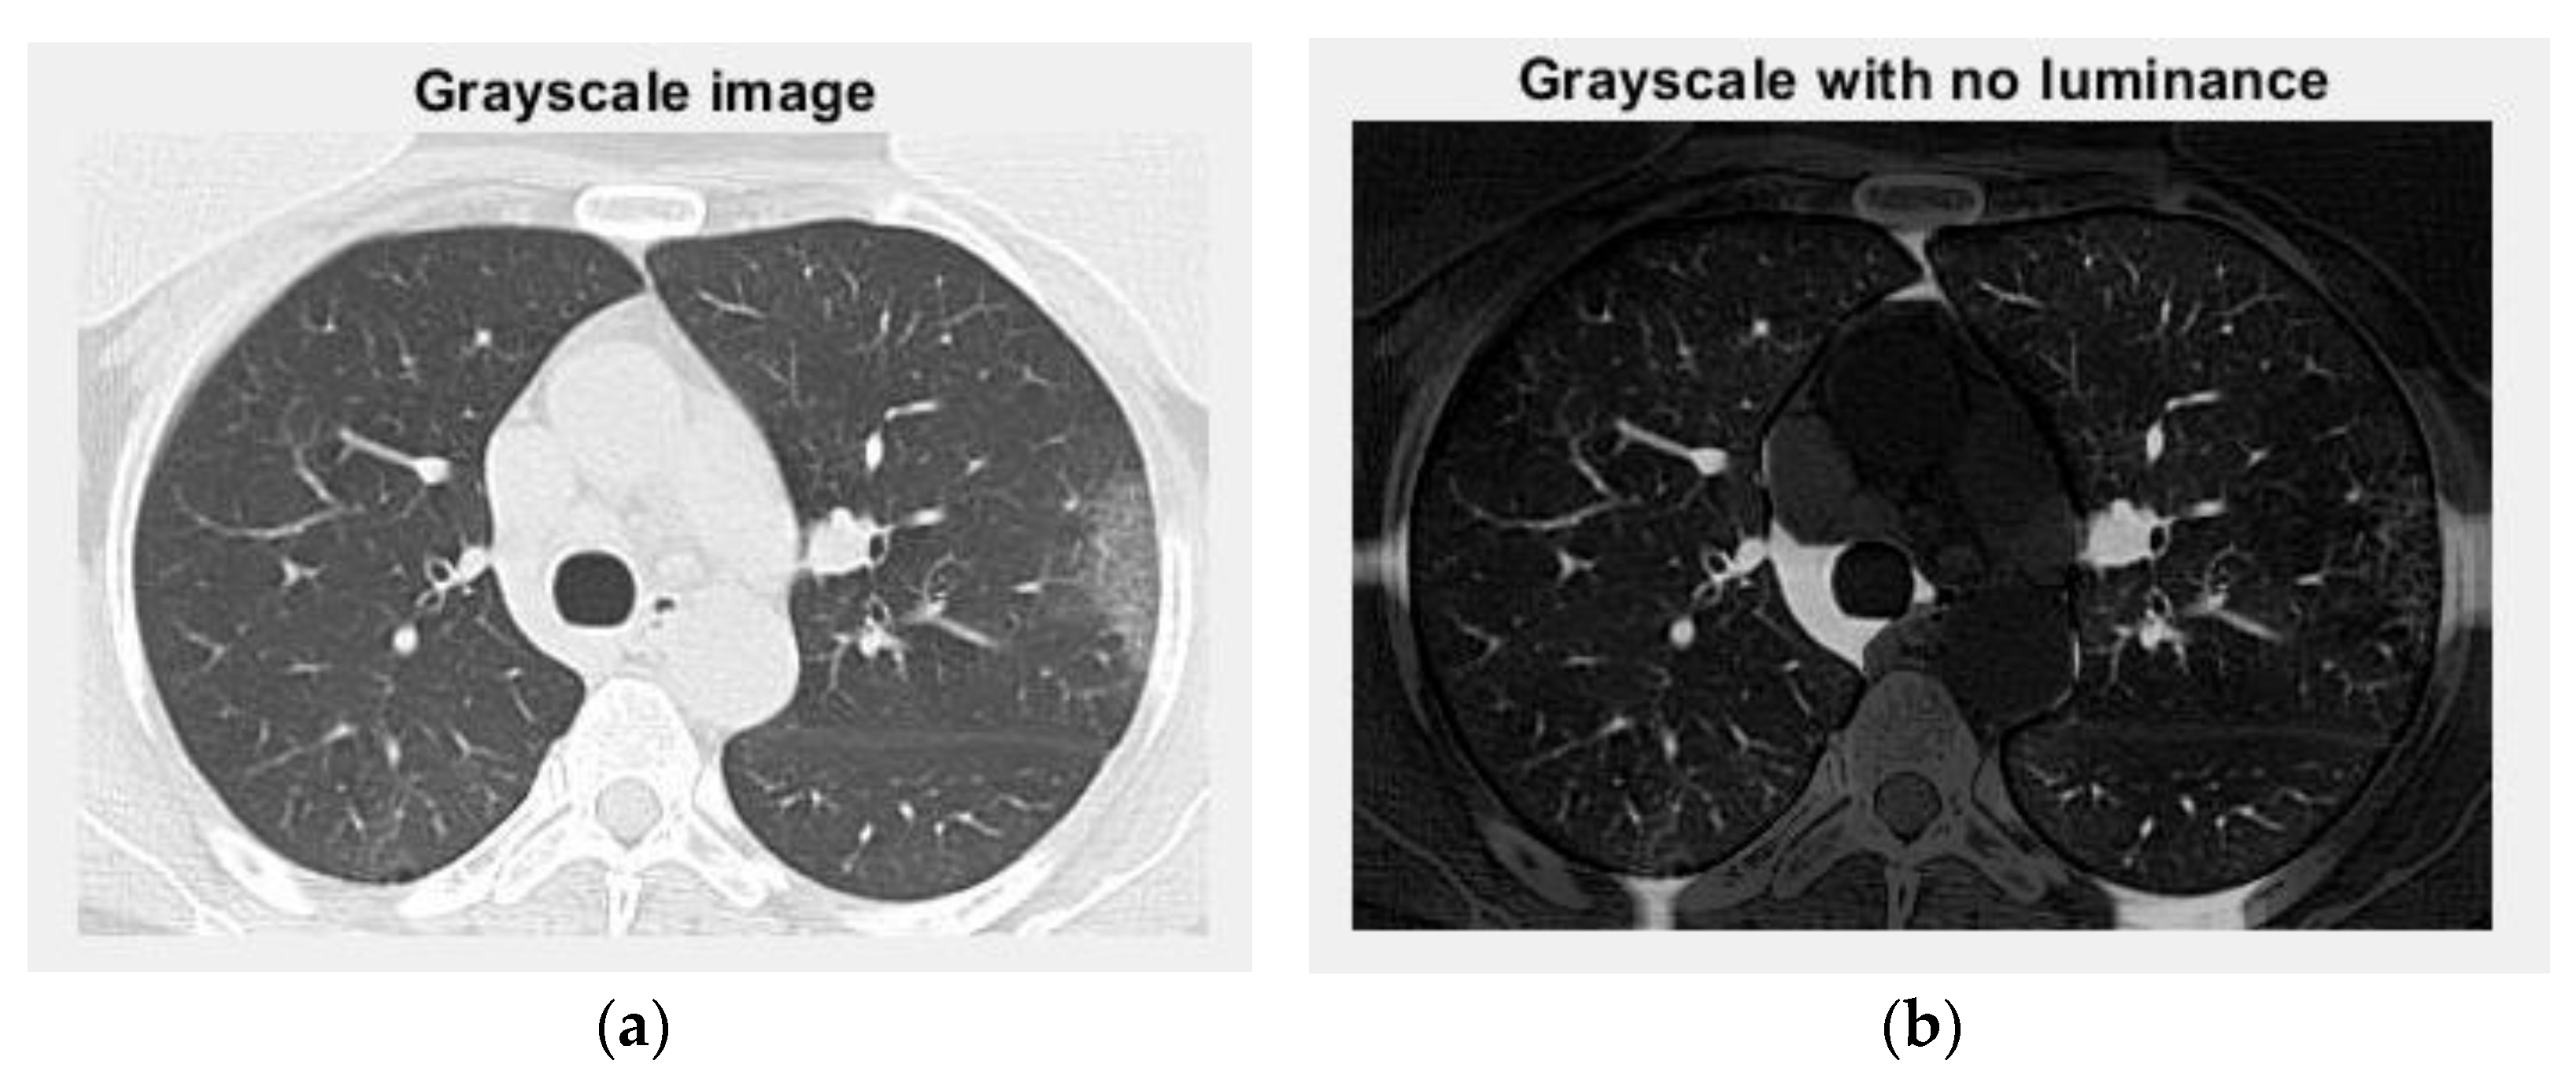

The voxels are usually utilized in scientific research to precisely and quickly focus on volumetric data [24,25]. In a voxels-founded structure morphology, condensation differences in the lung texture can be confronted utilizing the voxels, as seen in the figure above. Figure 12 and Figure 13 are the grayscale images with and without luminance of the COVID-19 lung CT image, respectively, and the filtered versions of the COVID-19 lung CT image.

Figure 12. Grayscale versions of the COVID-19 lung image: (a) grayscale image and (b) grayscale with no luminance.

Figure 20. Grayscale versions of the non-COVID-19 lung image: (a) grayscale image and (b) grayscale with no luminance.